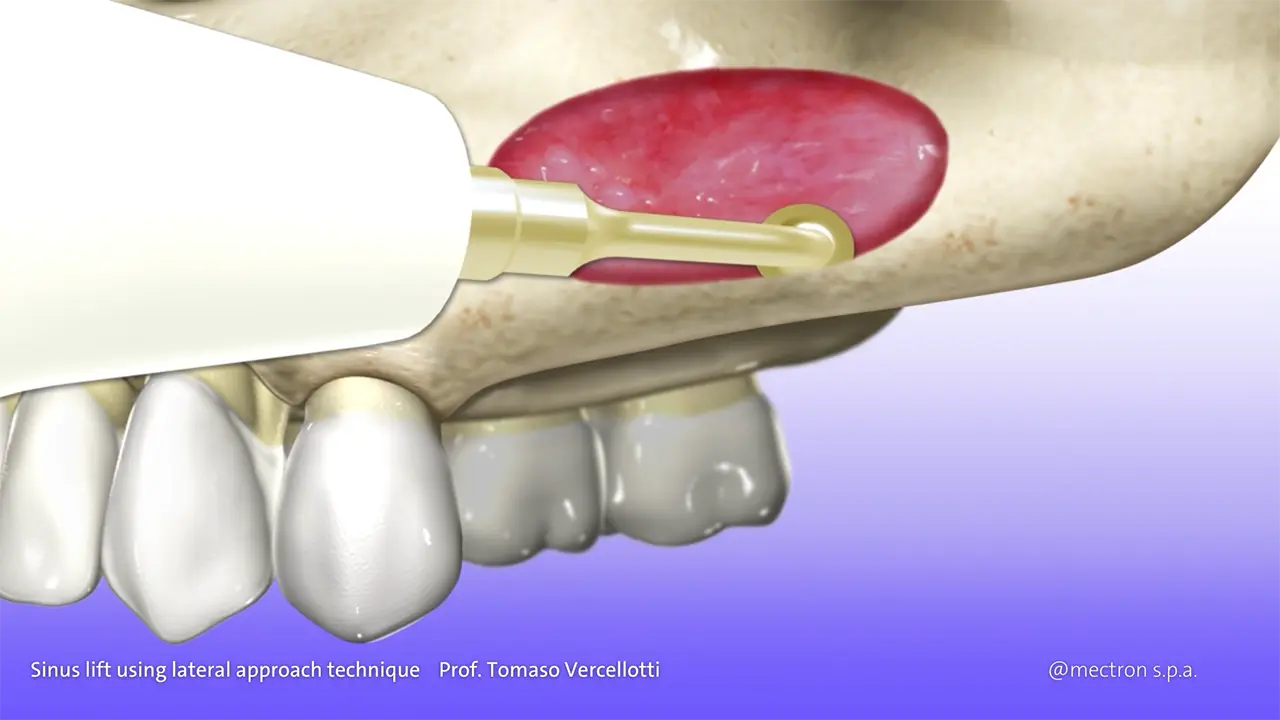

PIEZOSURGERY® Sinus lift

Prof. Tomaso Vercellotti

Sinus lift using lateral approach technique